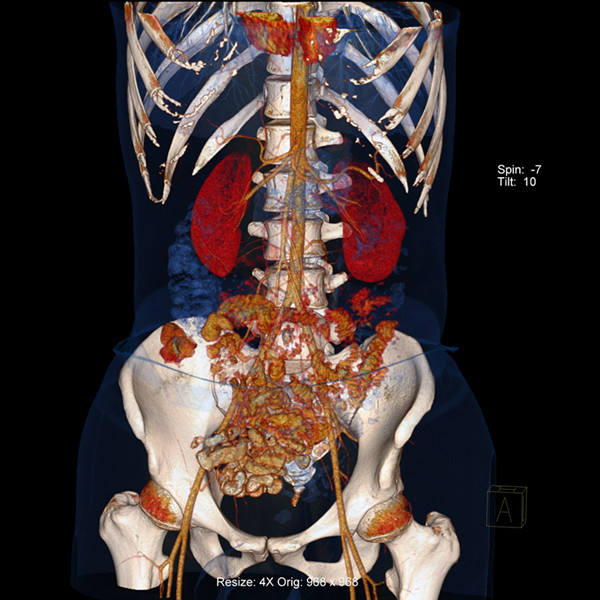

炫速雙源CT是目前世界上最先進的CT設(shè)備之一。它采用兩套64排圖像采集系統(tǒng),結(jié)合“飛焦點”技術(shù),并且有超高的旋轉(zhuǎn)速度,能夠在極短的時間內(nèi)完成掃描,為病人提供“綠色” CT 檢查。它的特點是炫速掃描技術(shù) (Flash Spiral),即大螺距的螺旋掃描,可以在一秒鐘之內(nèi)完成掃描,同時輻射劑量極低。 它的主要特色掃描技術(shù)如下:

7、病人因胸痛急診時,快速獲得準(zhǔn)確的診斷是關(guān)鍵。對于具有極高時間分辨率的炫速雙源CT來說,不但可以輕松完成常規(guī)檢查,而且可以對特別嚴(yán)重的急診患者完成“一站式”診斷,對急性胸痛患者通過一次注射對比劑同時獲得冠脈CTA、肺動脈CTA及主動脈CTA,可明確胸痛病因是心臟冠脈疾病、肺動脈栓塞還是主動脈夾層,具有非常實用的臨床價值。

9、冠狀動脈旁路搭橋術(shù)后的評價:橋血管閉塞是冠狀動脈搭橋術(shù)后常見的并發(fā)癥,炫速雙源CT可進行搭橋術(shù)后的常規(guī)復(fù)查。經(jīng)過檢查,當(dāng)發(fā)現(xiàn)冠脈血管有病變時,可進行冠狀動脈造影,以確定最佳治療方法。 |